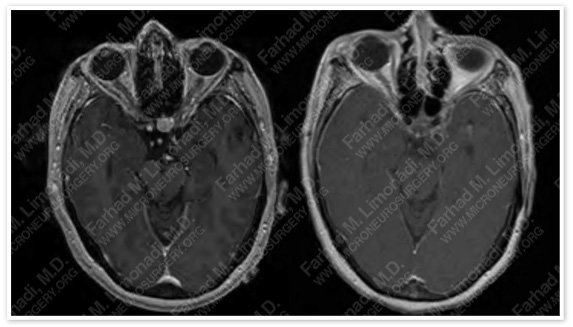

Post-op Imaging

Post-op MRI shows complete resection of the tumor with no injury to surrounding neurovascular structures.